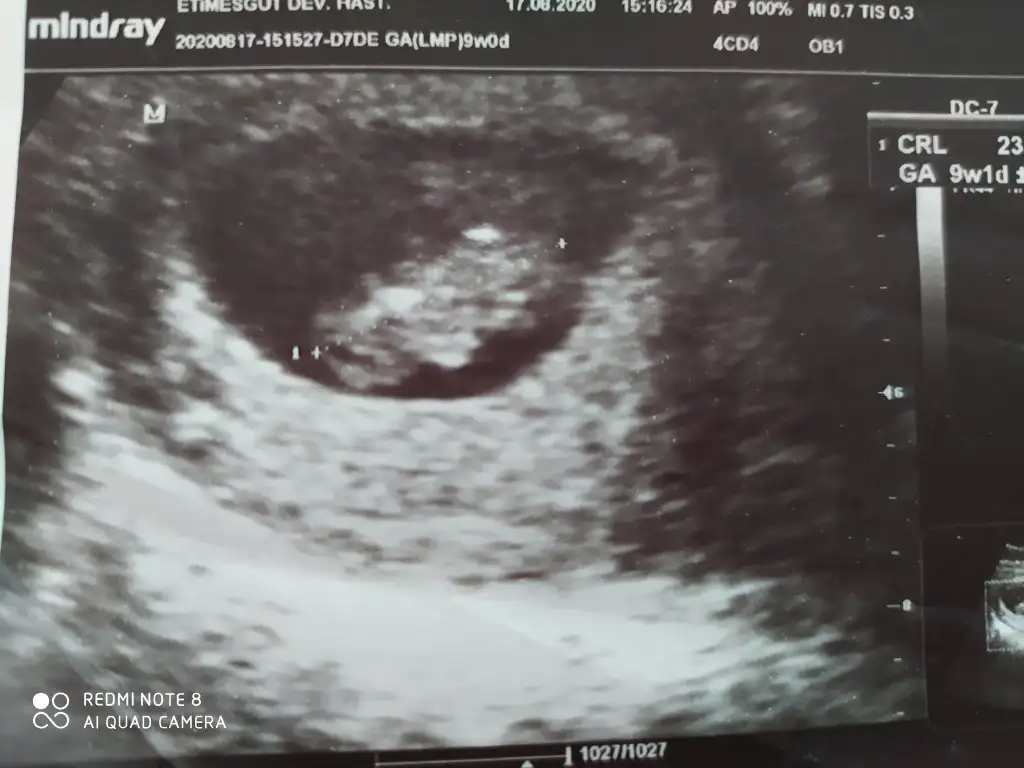

Çift yumurta dedi doktorumuz ama bilemiyorum ikiz olduğuna soktayım hala😬 yaa normal ultrasonu almayı unutmusum heyecandan ayrıntılı olanlar var ama 10haftalık var onu paylaşıyorum anlasılır belki😇 ne güzel ikiz kız bakımında zorlandınızmı😅😇 bende ilk hamile olduğumu öğrendiğimde kız hissediyordum ama ikiz olunca bir kız bir erkek gibi geliyor ama gönül öyle istiyor diyede olabilir🙈 sağlıklı olsunlar da ama bi merak oluyor illa işte😊

Eklentiler

• IMG_20200924_131022.webp

IMG_20200924_131022.webp

31,3 KB · Görüntüleme: 56

İkiside kız görünüyor ama bu haftalar yanitir siz 11 12 13 haftalar paylasin